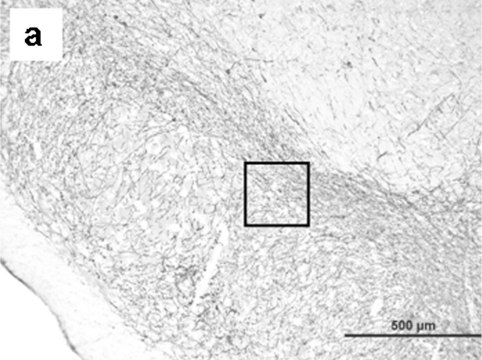

Immunohistochemistry:

A previous lot of this antibody was uesd at 1:100-1:1,000 dilution, 4°C, for 1-3 days. Stains both fresh frozen and paraffin embedded tissue samples by indirect immunofluorescence and immunoperoxidase.